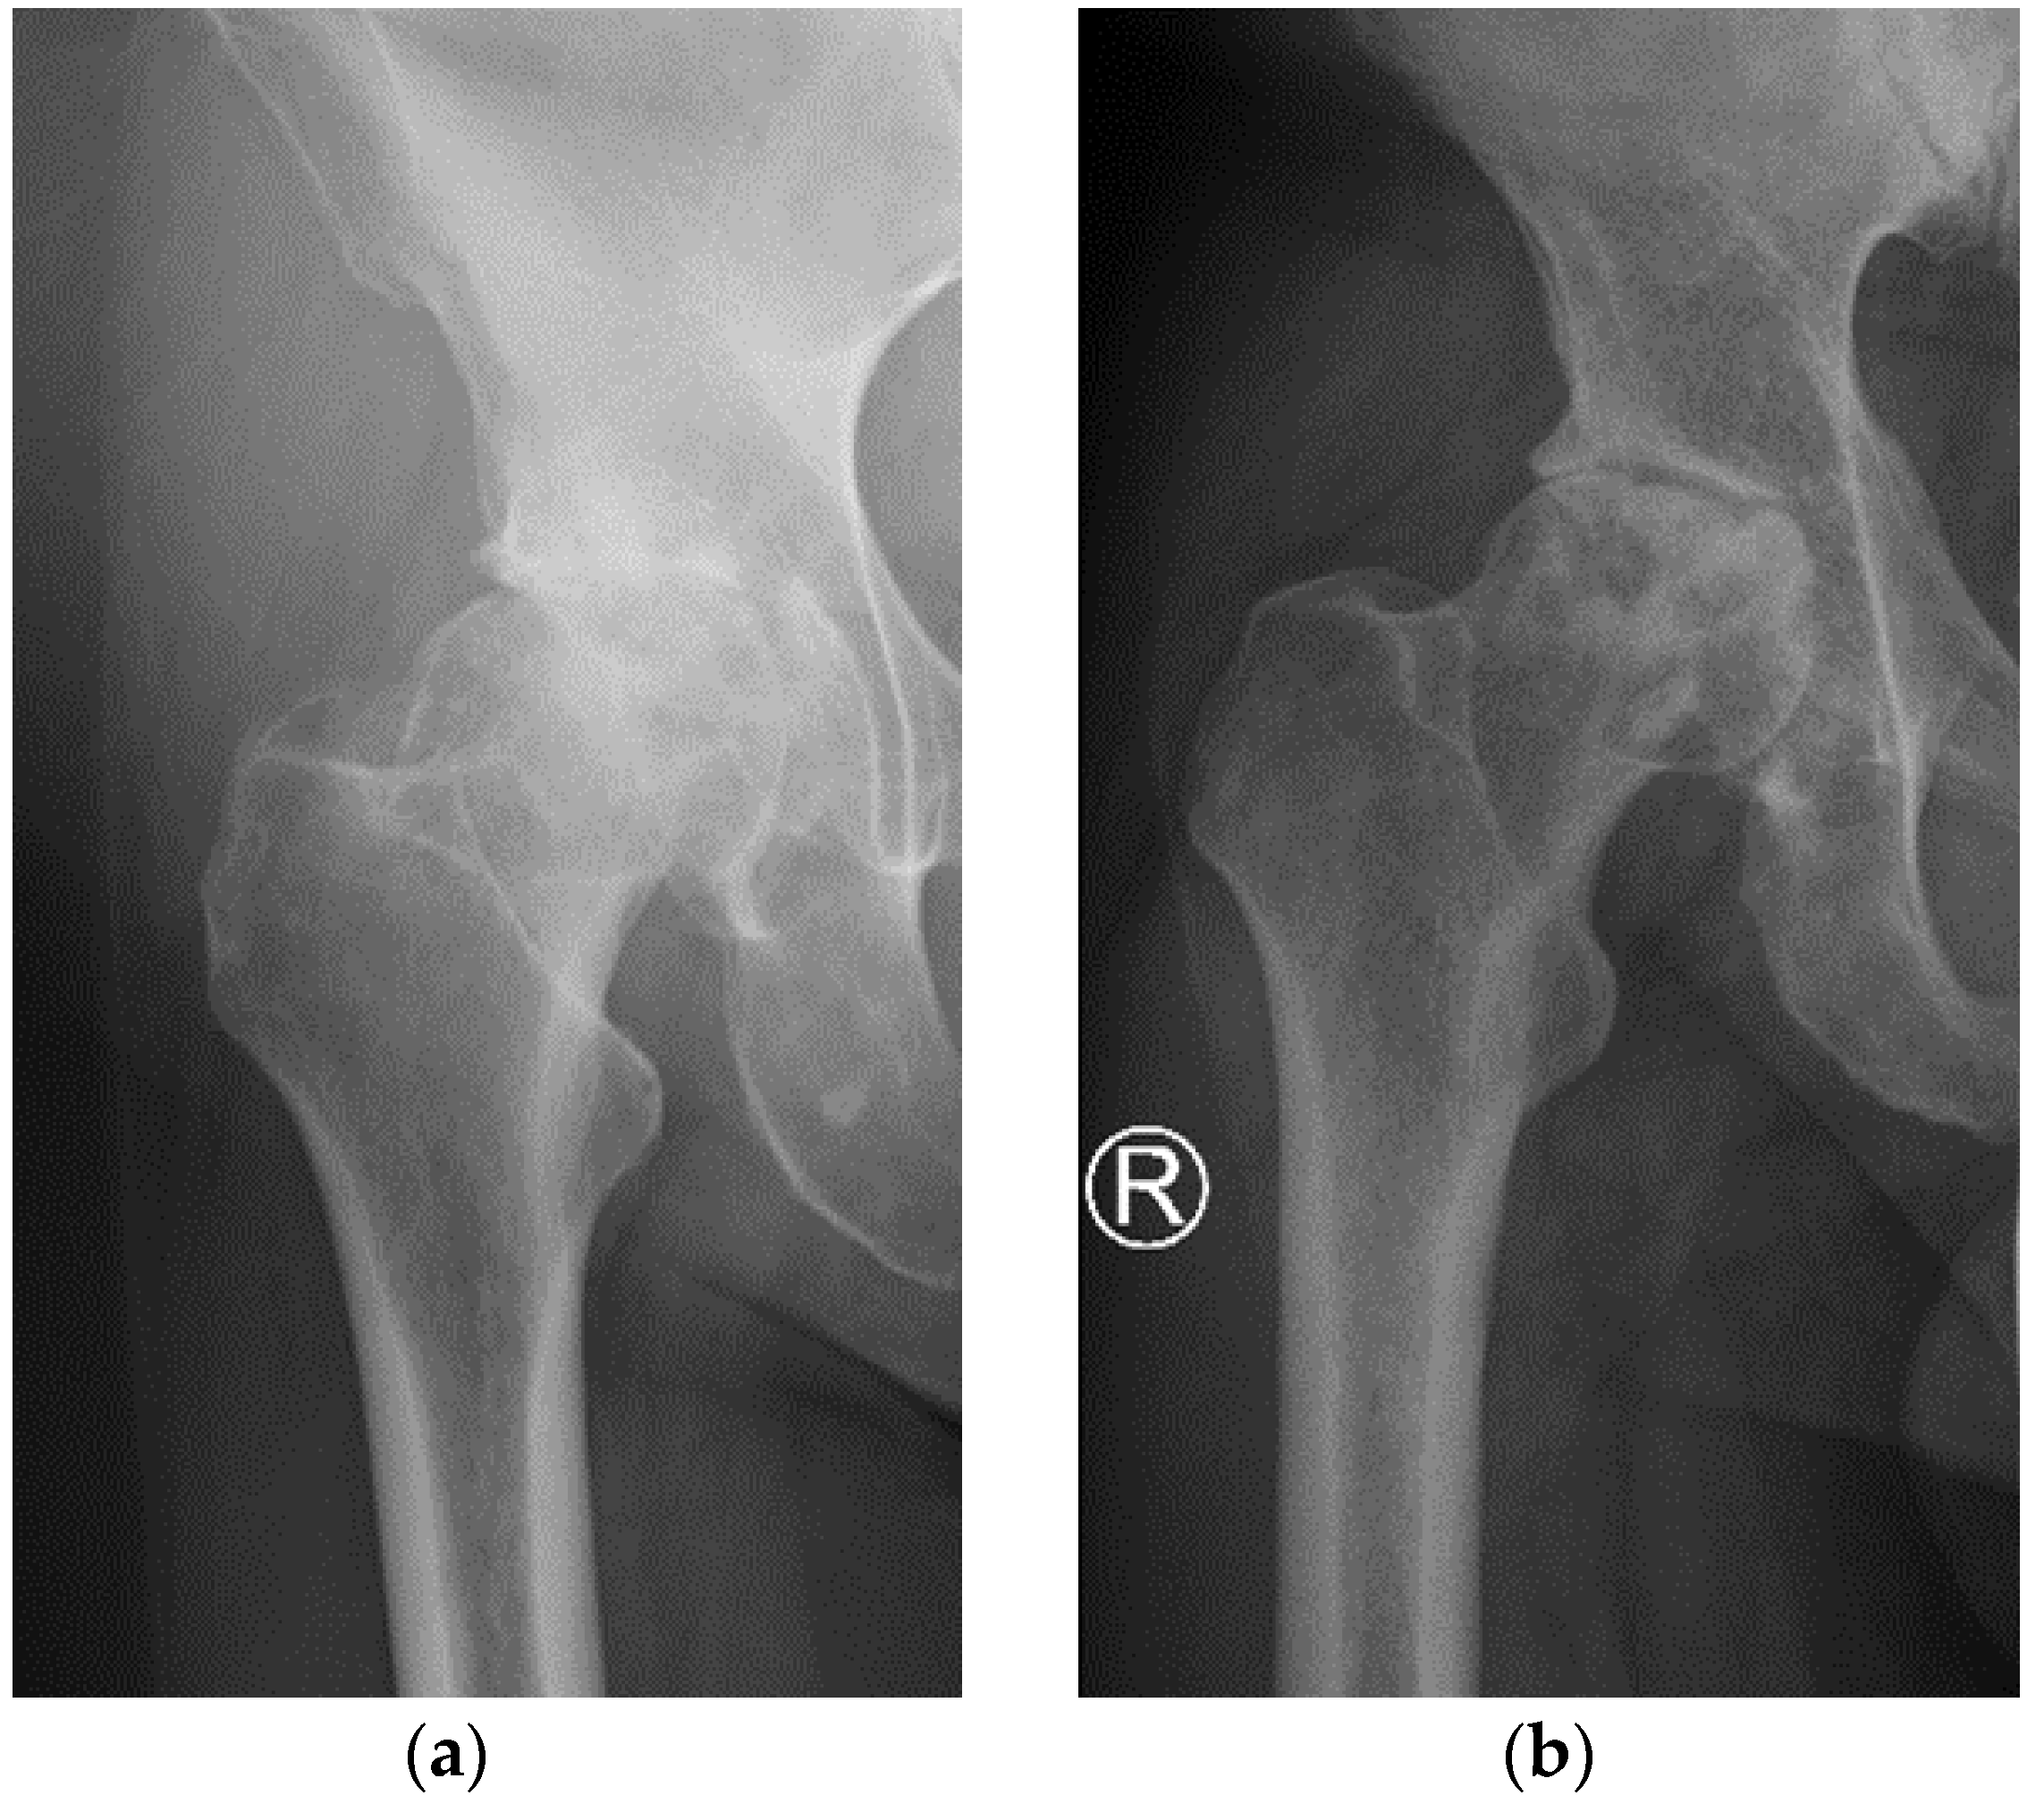

2.2. Radiological and Pain Assessment

3.1. Characteristics of the Patients